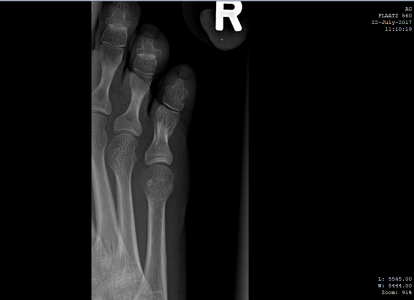

Здравствуйте! Прошу помощи. Прошло 18 дней со дня перелома мизинца (4 июля), к сожалению,находясь заграницей так и не удалось попасть к нормальному врачу, ходила с примотанным пластырем к соседнему пальцу, синяк почти прошел, сегодня сделали снимки - по -моему разницы никакой, угол отломка не изменился, при опоре на мизинец чувствуется давление и распирание внутри, будто эта кость торчит там внутри что-ли, как мешает что-то, при опоре отъезжает и смотрит немного в сторону, расстояние с соседним пальцем больше, чем на здоровой ноге. Думаю насчет возврата на родину и лечения в Москве. Вопрос - можно и нужно ли его еще как-то вправить, какой предельный срок? Не станет ли хуже от этих правок?

Забыть и ходить как есть? Какие последствия если не так срастется? Дискомфорт при ходьбе будет? Для меня это очень важно, заранее благодарю за ответ. Первый снимок - сразу после перелома 4 июля, остальные - 22 июля.